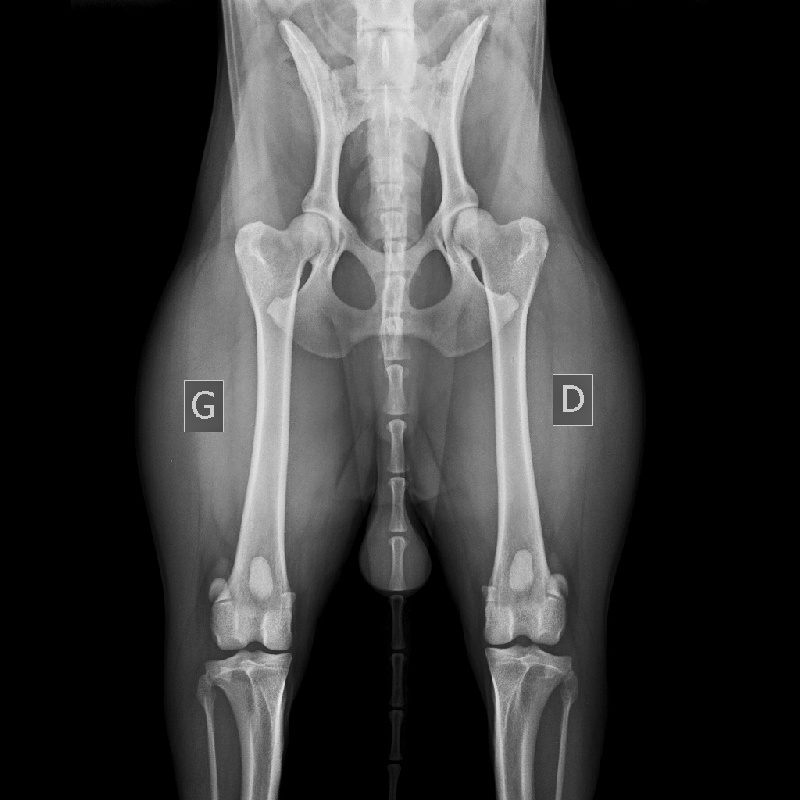

Chien Berger Belge Tsar de la Criniére Noire

tsar de la criniere noire mondio 2 et ring 2 point pour ring 3 pas de dysplasie et aucun signe d'arthrose

Dysplasie - AADysplasie des coudes - 0-Dys absTares Oculaires - exemptManque de dents - Aucune